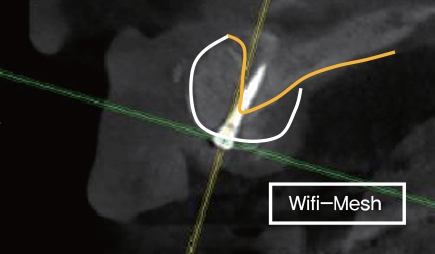

Wifi-Mesh와 BOSS Screw를 이용한 수직 골 증대

① 치조골량 부족으로 Implant 식립 불가

② BOSS Screw 중앙에 고정

③ 골이식 시행

④ Cover를 이용하여, Wifi-Mesh를 Screw에 장착